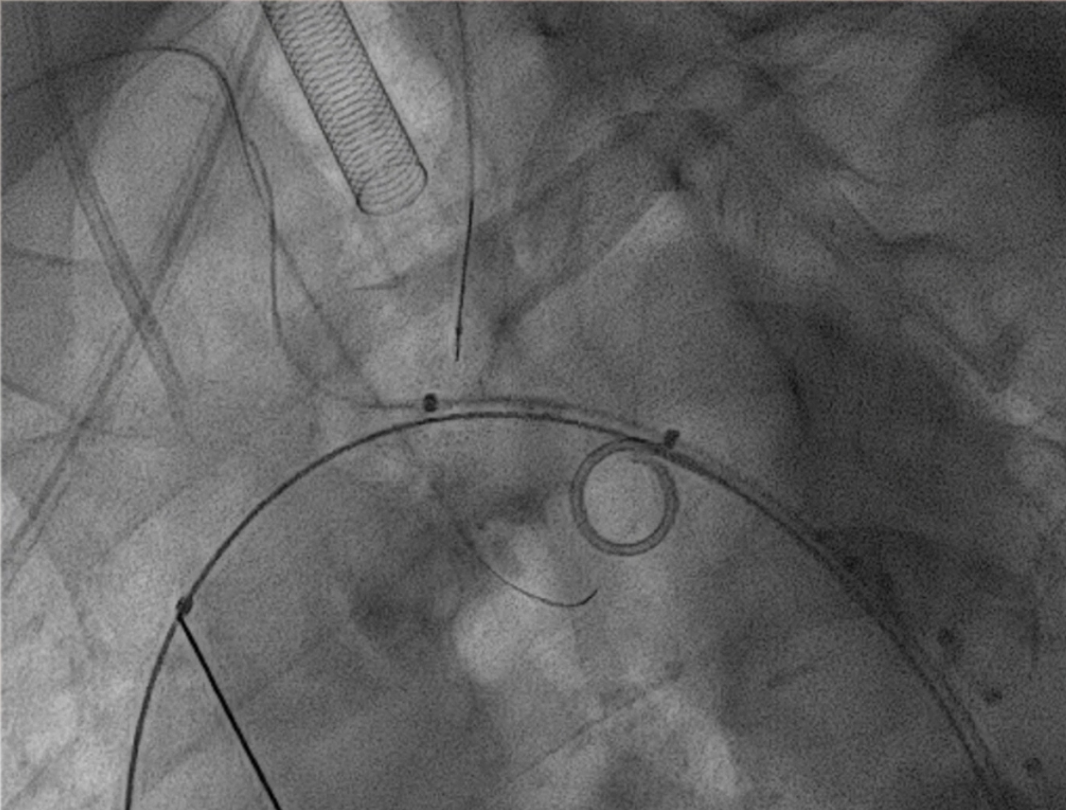

3. 关键分支处理环节,分支导丝超选与抓捕建立分支导丝通路

使用4F 导管和抓捕系统,分别超选弓上三分支(无名动脉、左颈总、左锁骨下动脉)

14系统导丝经防缠绕导管引出至右侧股动脉输送鞘外,建立分支导丝通路。

无旋转状态下撤出防缠绕导管。

将主导丝与导管准确卡入对应分线器卡槽内,撤出防缠绕导管内的导引导丝,各分支导管分别接入对应的分支导丝。主导丝连接支架输送系统,各牵引导丝从弓上引出并连接牵引器,通过牵引器保持适当张力,确保支架手柄编号与防缠绕导管手柄编号一致。

沿超硬导丝将主体缓慢送入主动脉弓部,透视下确保导丝无缠绕。

调整支架位置,确保主体分支支架对应无名动脉、左颈总动脉及左锁骨下动脉开口位置满意。